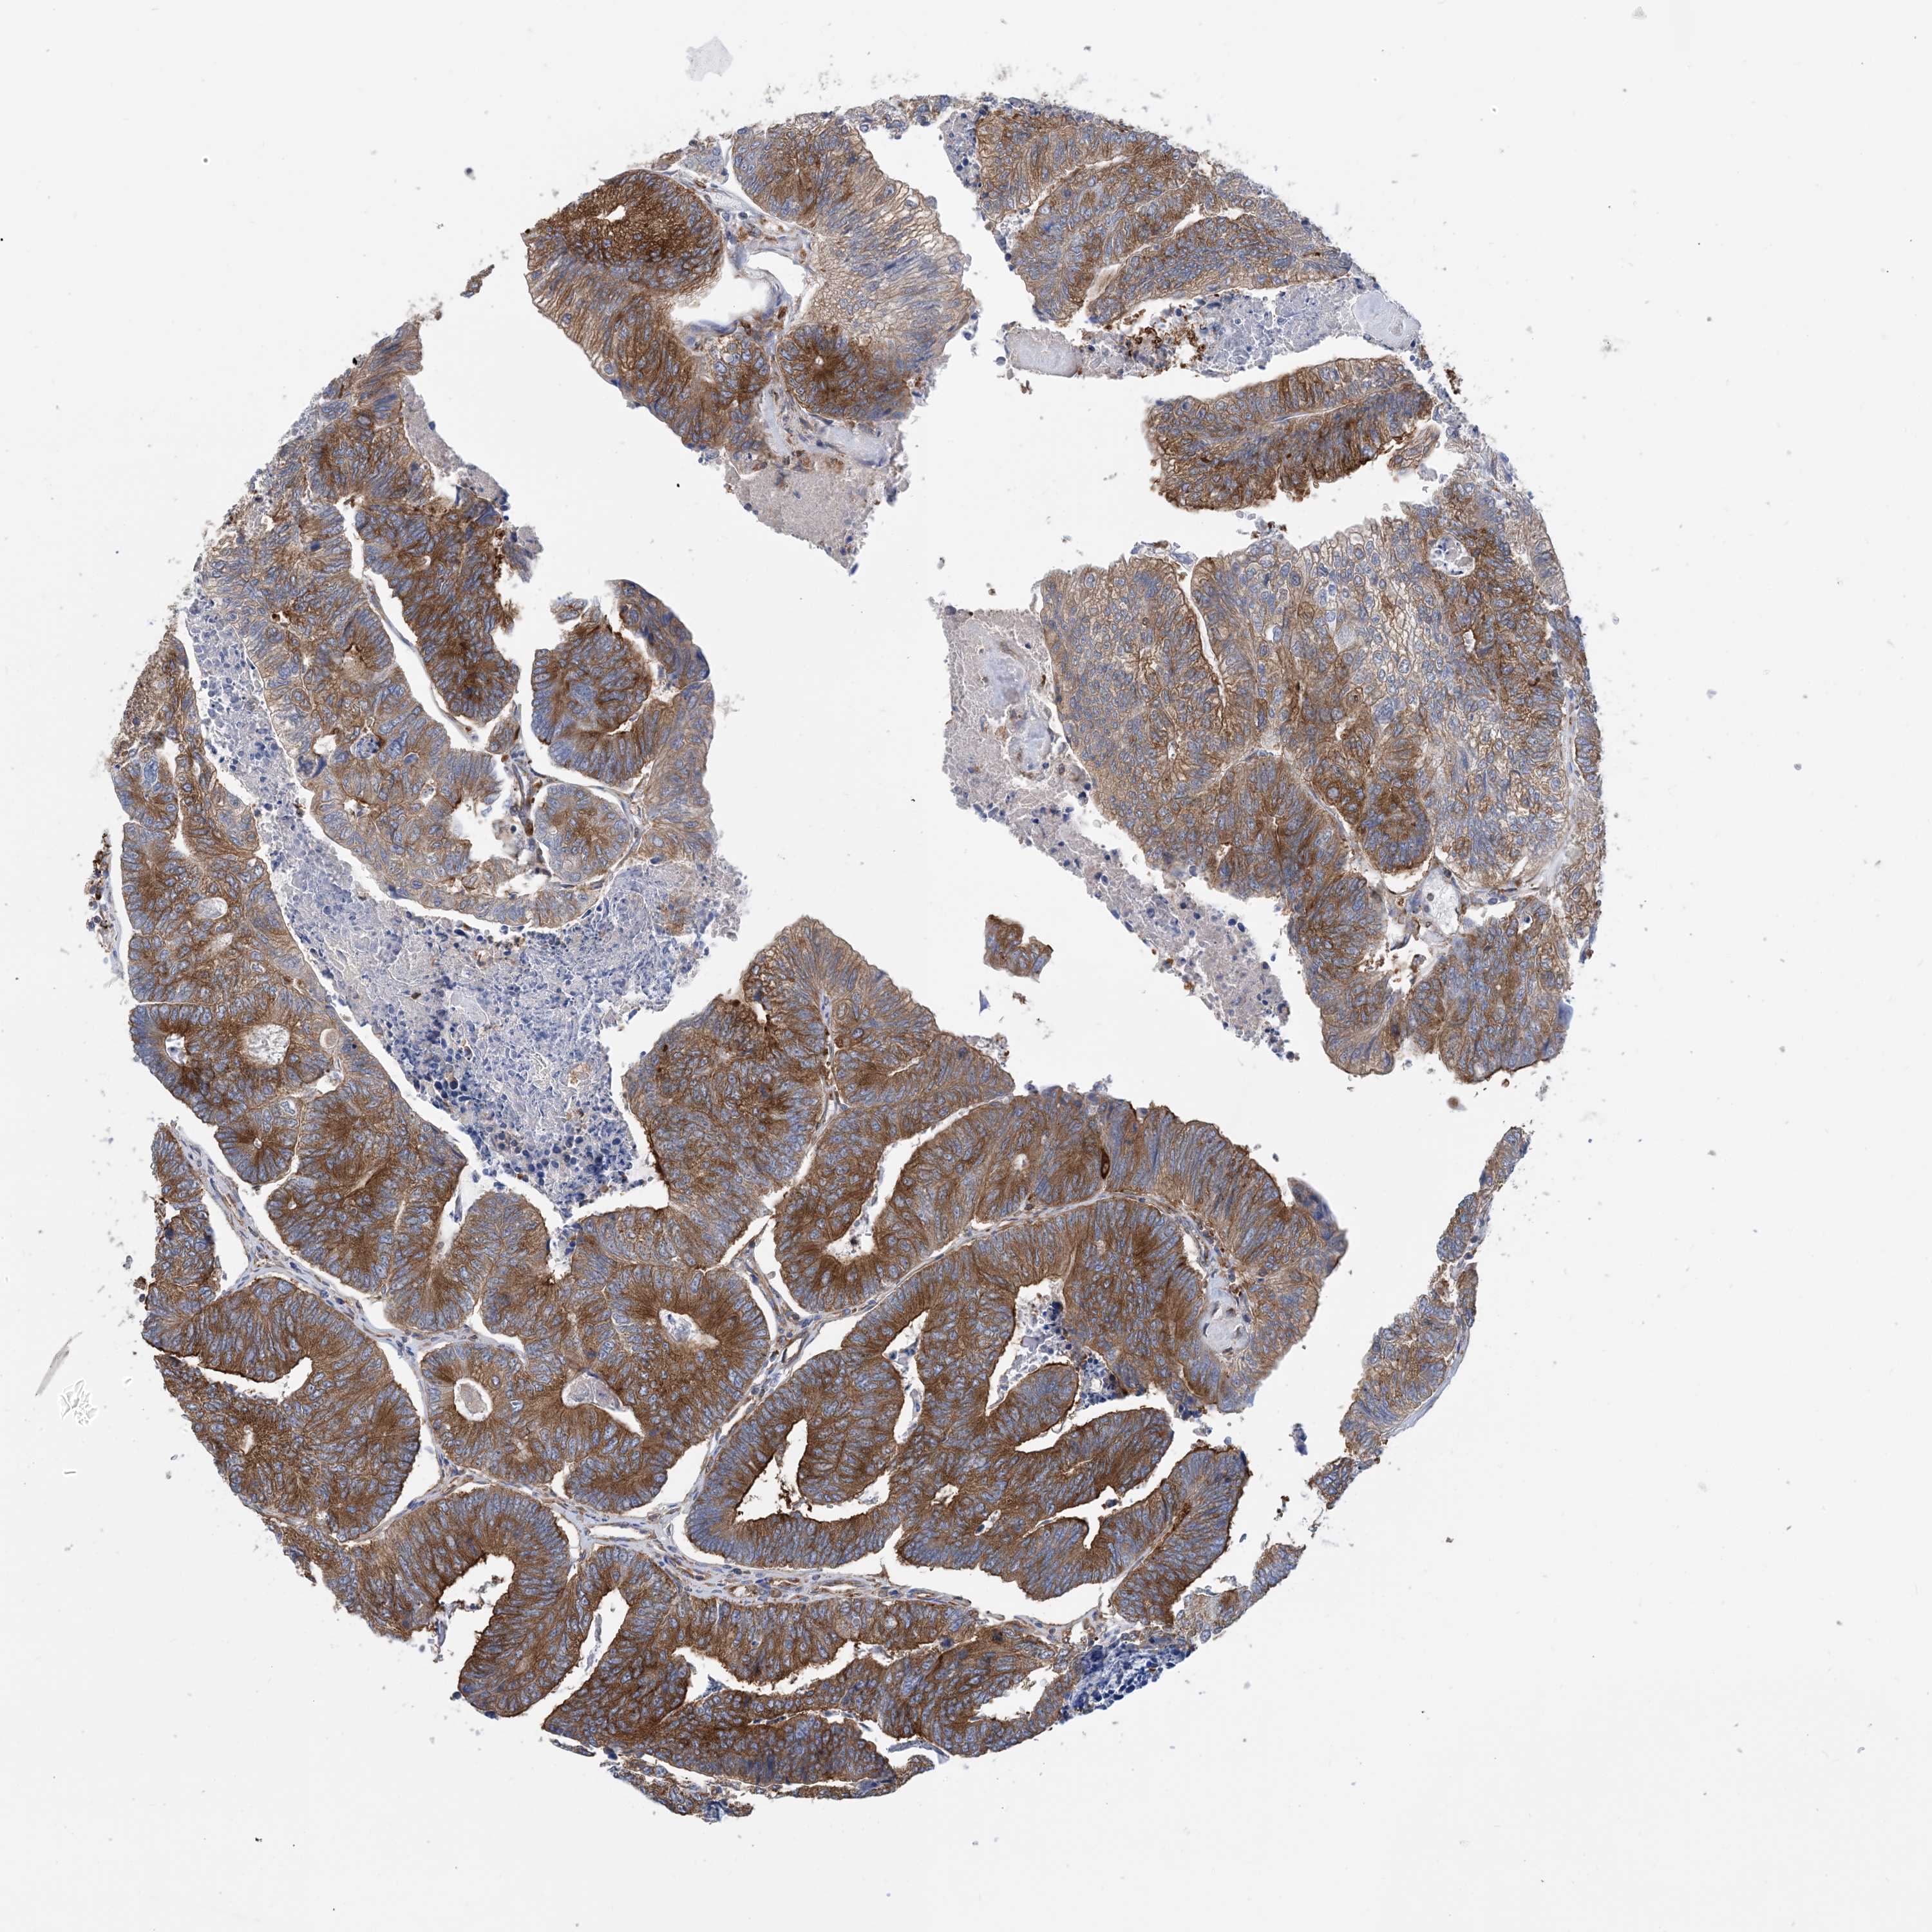

CANCER COLORECTAL CANCER Show tissue menu

Colorectal cancer

Human cancer

Colon adenocarcinoma